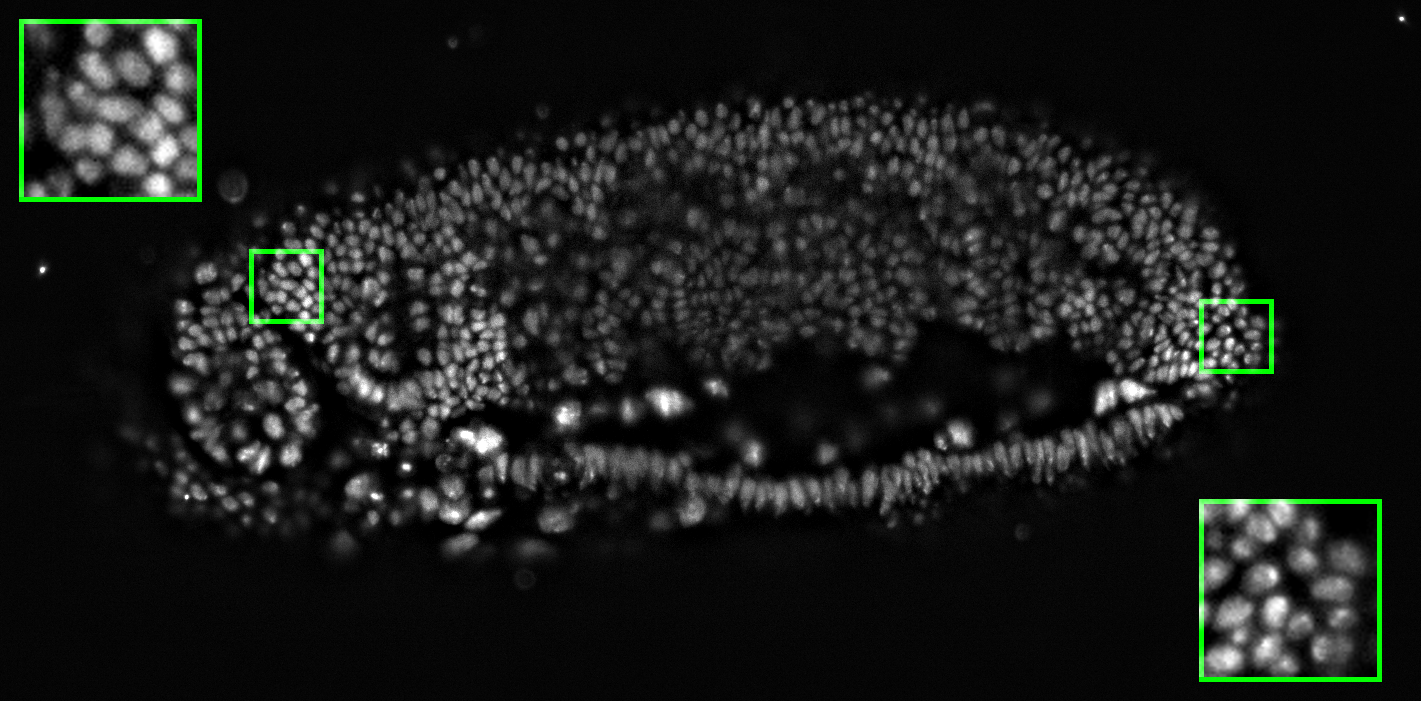

As mentioned above, it is hard (any potentially undesirable) to directly build a GDP from biomedical images. We hence learned the prior from natural-scene images, but validate it here on biomedical images. We first show stability of the present GDP for biomedical images. For this, we collected a small dataset of biomedical images, including X-ray, MRI, electron microscopy, and fluorescence microscopy images. Some examples are shown in Figs. 10 and 24.

9.1 Image naturalization

Remapping the gradient field of any image to match the GDP of natural-scene images, and then reconstructing the output image is called image naturalization, because the output image will have a gradient distribution that matches the one of natural-scene images. The naturalized output image hence looks more “natural”. The workflow is shown in Fig. 23. Since the GDP correlates with image quality, this makes the image look more appealing. We hence propose to use image naturalization as an alternative to histogram equalization when displaying images to a human observer. Image naturalization enhances contrast by solving Eq. 2 with hard GDP constraint. Some examples of microscopy images (left tile of each panel) and their naturalized versions (middle tiles) are shown in Fig. 24 along with the naturalness factor of the original image. The histogram-equalized images are shown in right tiles for comparison. The first row shows four fluorescence-microscopy images. The second row shows three electron-microscopy images and one fluorescence image. All images were collected from publicly accessible web pages; credits are in parentheses. Here we use the simple linear function, amounting to a straightforward rescaling of the image, albeit with a good, “natural” scale factor as determined by the GDP. In all cases. the naturalized image looks more appealing than the histogram-equalized image, and suffers from less background artifacts.